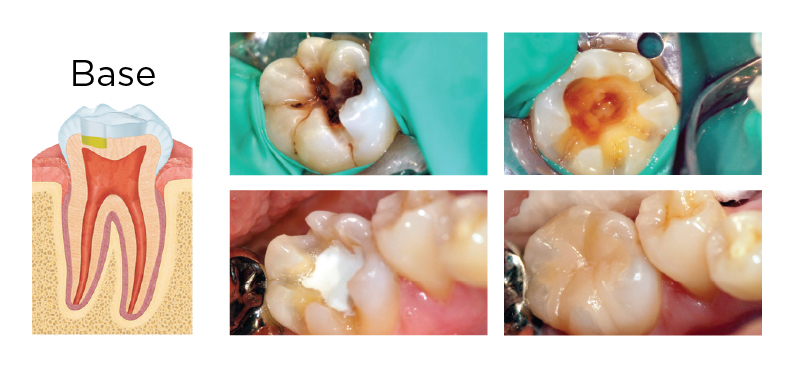

MTA AS A BASE

Fig. 1. A deep carious lesion (greater than two-thirds into dentin, upper left) was treated with an indirect pulp cap (base). Rubber dam isolation was utilized in case a pulp exposure occurred. After caries removal (upper right), 1.5 mm of SmartMTA was placed and allowed to set. Final restoration was completed with a Tesera resin inlay (bottom right).